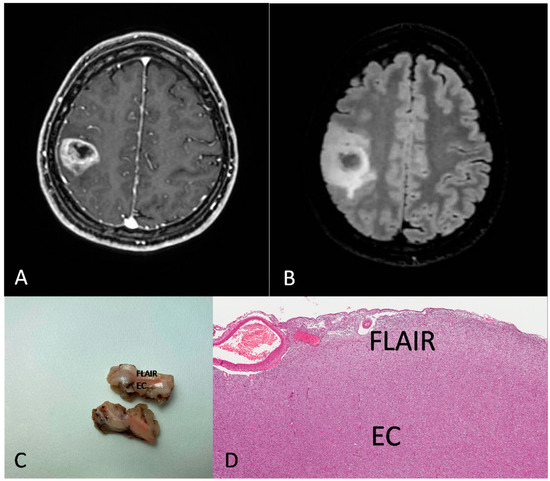

Figure 2 and Figure 3 show the MRI features, the gross findings and the histopathology of two cases from our series.

Figure 3.

Preoperative MRI from a 31-year-old woman. (A) Axial section of a T1-weighted sequence with gadolinium showing a rolandic tumor with necrotic core and ring enhancement. (B) FLAIR sequence showing a hyperintensity beyond the EC. (C,D) Gross image (C) and histological medium magnification (D) showing both EC and FLAIR region from the excised mass ((D) H&E; original magnification 50×).